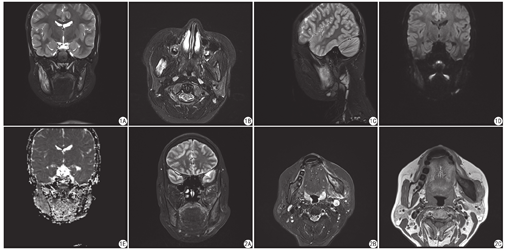

本组9例患者均有不同程度的下颌骨受累,上颌骨均未见受累。①骨髓水肿(图1A、图1B、图2A):9例均累及下颌支、下颌角,8例累及邻近下颌体部,2例髁突受累,冠突显示欠佳,但冠突区未见明显骨髓水肿,其中1例为对称性弥漫性受累,其余为非对称性;②骨质肥厚(图1A、图1B、图2B):7例累及下颌支及下颌角,6例累及下颌体部,其余6例均累及髓质,皮质线均匀完整;③4例骨髓水肿周围软组织出现少许水肿信号,仅1例颞颌关节周围肌群少许水肿,其中1例周围咬肌明显肿胀(图2B、图2C)。9例均出现多发淋巴结,表现为椭圆形、圆形,或不规则型(图1C)。1例出现上颌窦粘膜囊肿。其中1例(图1D、图1E)扩散加权成像示病变区未见明显扩散受限,ADC值为1.268×103 mm2/s,对侧正常下颌骨ADC值为1.240×103 mm2/s。

磁共振因具有良好的软组织分辨率,能够很好地提示临床病变活动性的骨髓水肿,以及病变周围软组织的受累范围,从而为临床治疗、随访提供帮助[2],但既往仅见个案报道[13,16,17]。本研究应用Dixon技术对下颌骨病变进行统一方案扫描,其能够利用同相位和反向位一次产生单独的"水"和"脂肪"信号图像,主要表现为非对称性骨髓水肿伴骨质肥厚、硬化,其中髁突受累少见。本研究中7例呈不对称的骨质肥厚,均为髓质肥厚,这与既往研究锁骨受累的表现一致,主要是由于骨髓水肿刺激骨质肥厚,早期主要为髓质受累,随后累及皮质,后期表现为皮髓质弥漫性增厚[2]。另外,随访研究发现,即使应用部分下颌骨切除术,随着时间进展,病变依旧会进展至对侧。既往CT研究所示颌骨受累主要表现为非对称性骨质肥厚、硬化,伴有散在多发斑片状骨质破坏,而骨皮质一般相对完整[2,4,5,14,17],也有报道示病变以骨质破坏为主,而肥厚、硬化不明显,且可累及骨皮质,但很少会有颞颌关节的严重破坏和强直[8,16,17,18]。另外,CT可进行三维重建,对病变进行整体评估[4,6]。与CT比较,本研究中磁共振显示骨质硬化欠佳。既往研究表明中轴关节受累均出现脂质沉积,提示病变修复[2],但本研究中所有病变均未见脂质沉积。本研究中5例出现邻近软组织少许水肿,仅1例累及周围肌群,且仅限于咬肌肌群,未见文献报道中的颅底肌群的大范围受累[18]。周围诸牙及周围牙龈均未见明显水肿,仅1例出现上颌窦粘膜囊肿,提示病变起源于下颌骨本身,而非邻近易感部位的累及[5]。所有病例扫描范围内均可见多发淋巴结,数目虽多,部分增大短径超过1 cm,但一般呈椭圆形,且无融合倾向。1例行扩散加权成像检查,提示病变未见明显扩散受限,这与既往研究中骶髂关节受累可出现扩散受限不一致[19],下颌骨受累的扩散加权成像表现需要进一步研究。本研究也有一些局限性,如病例数相对较少,缺乏对照组,无钆增强图像等。